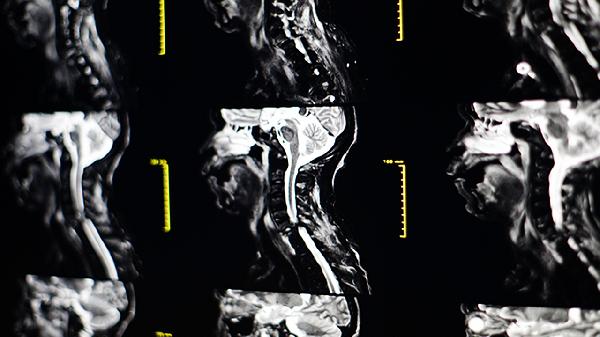

颈动脉夹层可能由外伤、高血压、结缔组织病、动脉粥样硬化、血管发育异常等原因引起。颈动脉夹层是指颈动脉壁层分离形成假腔,可能导致脑缺血或卒中。

颈动脉夹层患者应避免剧烈颈部活动,戒烟限酒,控制血压血糖。急性期需绝对卧床休息,恢复期可进行适度有氧运动。饮食以低盐低脂为主,多摄入富含维生素C和维生素E的新鲜蔬菜水果。定期复查血管超声或磁共振血管成像,监测血管修复情况。出现新发头痛、视力改变或肢体无力等症状需立即就医。